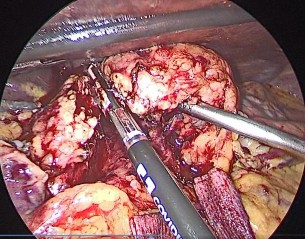

Hình 4.1. Cắt động mạch vị tá tràng Nguồn: BN Đỗ Văn M, 67 tuổi. Mã BA: 19-03-00991 BM |

Để tìm và thắt động mạch vị tá tràng, chúng tôi thường bắt đầu bằng việc phẫu tích lấy hạch dọc động mạch gan chung và động mạch gan riêng. Động mạch vị tá tràng thường là chỗ chia của động mạch gan chung hướng xuống phía dưới đến bờ trên tụy. Động mạch vị tá tràng được thắt qua nội soi bằng clip nhựa (hemolock) 5 mm trong tất cả các trường hợp, sau đó cắt trực tiếp bằng dao hàn mạch hoặc dao siêu âm. Một trường hợp chảy máu tuột clip (3,3%) trong khi phẫu tích được xử lý bằng nội soi (Bảng 3.18). Trong nghiên cứu của Boggi (2014) qua 502 trường hợp, các biện pháp cắt động mạch vị tá tràng được áp dụng là kẹp clips đơn thuần (n = 274; 54,5%), dùng ligasure đơn thuần (n = 100; 19,9%), ligasure + stapler mạch máu (n = 50; 9,9%), clip

+ buộc chỉ (n = 35; 6,9%), stapler mạch máu đơn thuần (n = 14; 2,7%), hàn mạch bằng sóng radio (n = 11; 2,1%) [50].